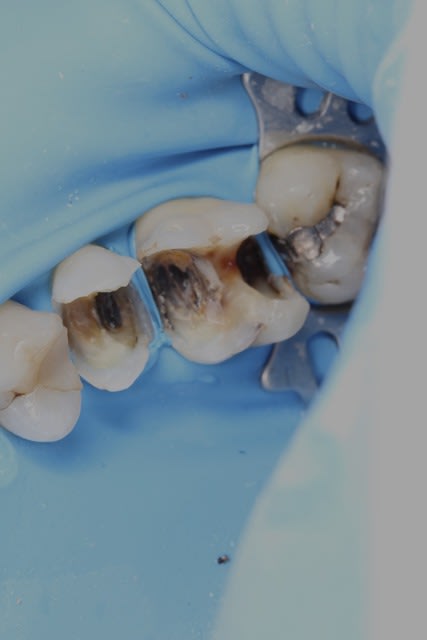

Effectivement non, celles là elles sont garanties rien du tout. On est même prévenu que si elles durent 6 mois c'est bien. Mais je constate que même ça ça dure plus longtemps...Y'en a une j'aurais vraiment dû prendre des photos. Mais ça concerne des amputations, hémisections, et dents très très délabrées...

Désolé photos de portable... Mais des cas comme ça.